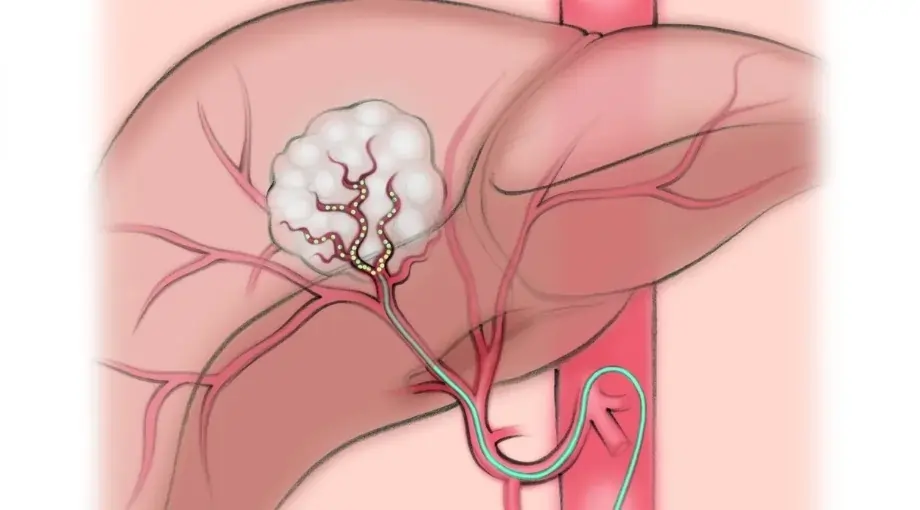

TACE (Trans-Arterial Chemoembolization)

TACE is used for cancers where targeted treatment inside the blood supply of the tumor offers better disease control. It helps slow tumor growth, reduce symptoms, and improve outcomes in patients who may not be suitable for surgery. This focused approach allows treatment to act directly on the tumor while preserving surrounding healthy tissue.

Trans-Arterial Chemoembolization (TACE)

Approved by the European Society of Medical Oncology (ESMO)

TACE is internationally recognised as an effective and well-established treatment for selected liver cancers. According to the European Society of Medical Oncology, TACE plays a key role in controlling tumour growth, improving survival, and managing symptoms. It is widely accepted as a standard, evidence-based, minimally invasive cancer treatment across Europe and globally.